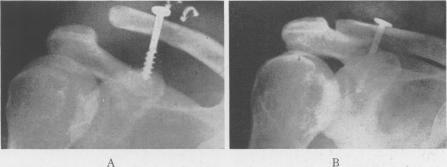

Acromioclavicular Dislocation: End-Results of Screw Suspension Treatment.

Ann Surg. 1948 Jan;127(1):98-111. doi: 10.1097/00000658-194801000-00009.